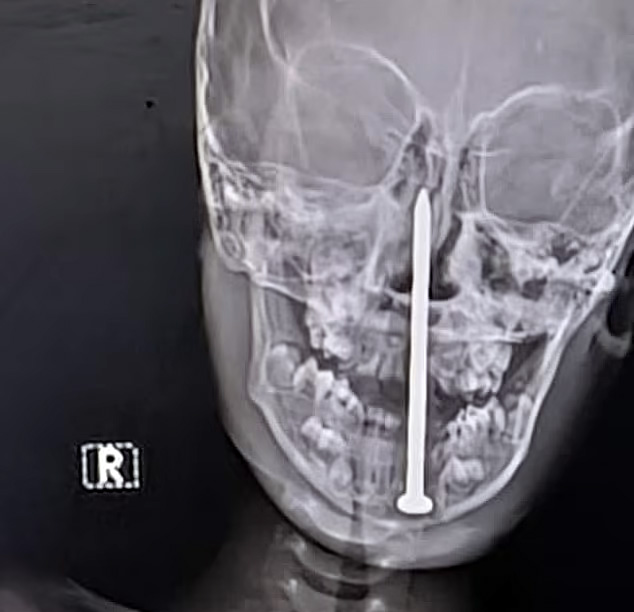

Семилетний мальчик из штата Раджастан перенес сложную нейрохирургическую операцию, во время которой врачи извлекли гвоздь длиной семь сантиметров из его мозга, пишет Daily Mail.

По данным местных СМИ, инцидент произошел, когда мальчик играл рядом со строительной площадкой, где споткнулся и упал носом на гвоздь. Его срочно доставили в больницу в Джайпуре, сделали компьютерную томографию и обнаружили, что инородный предмет почти на пять сантиметров проник в мозговую ткань.

Хирургическая бригада под руководством доктора Санкета Шармы провела более чем четырехчасовую операцию по удалению гвоздя. По словам врачей, чудом затронутыми оказались только лобные доли мозга, отвечающие в основном за когнитивные функции, а не за жизненно важные центры.